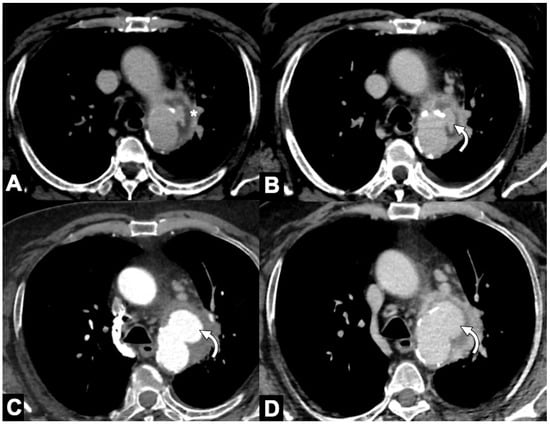

| 9 | Pericardial effusion/tamponade; pleural/extrapleural effusion/hemorrhage; mediastinal hematoma. |

| 10 | Signs of contained (peri-aortic bleeding) or free rupture. |